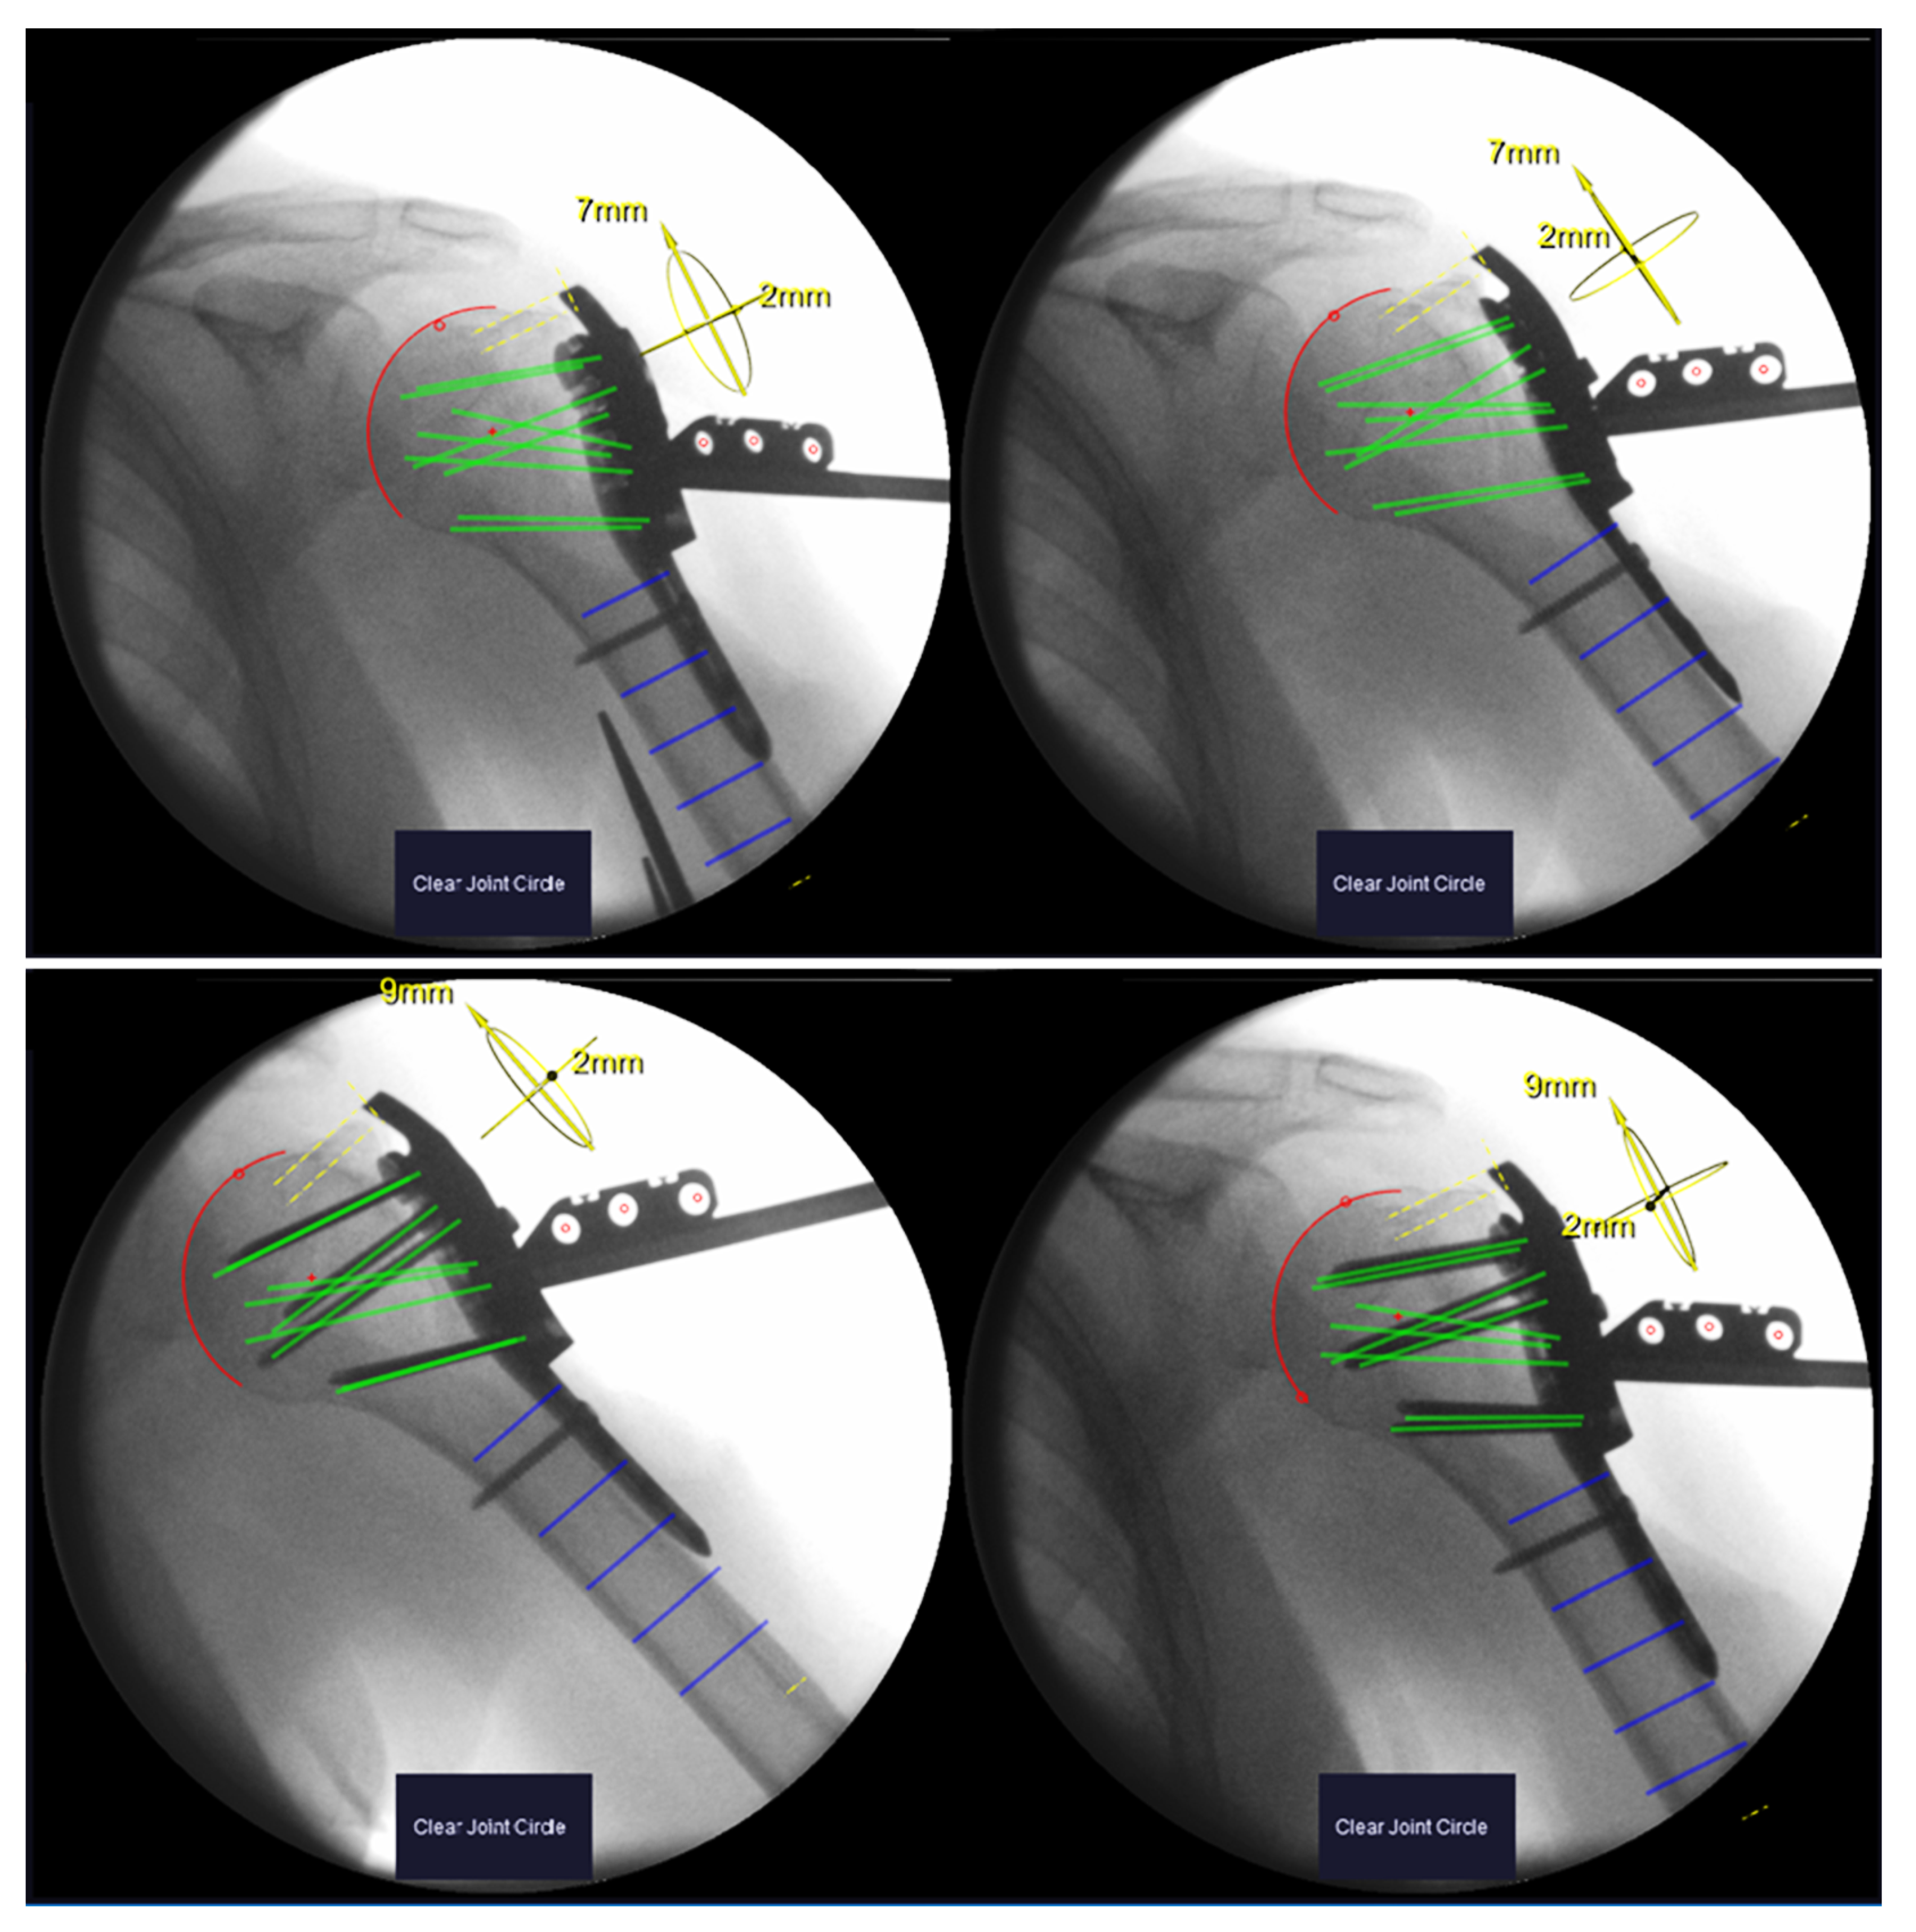

Image pairs from both stages were formed from the available X-rays and processed with the Xin1 software. An image pair was found valid if the view angle between the images exceeded 15°. So that several valid pairs could be formed, the pair with the largest view angle was selected. Screw lengths and plate positions were computed from the selected pairs for both stages. The plate position is calculated in relation to the anatomy, defined as the offset of the calculated center of the humeral head from the central screw trajectory (screw 7, D-Level) in cranial–caudal and dorsal–ventral directions (Figure 3).

Figure 3. Xin1 software output for an exemplary patient. Top row: image pair before screw insertion. Calculated screw trajectories depicted in green. Segmented humeral head in red. Bottom row: image pair after screw insertion (verification images). Green trajectories coincide with inserted screws.

Xray images of the remaining six patients underwent retrospective evaluation. Robust marker detection, humeral head segmentation and screw length determination were achieved in all image pairs. The view angle between the images of a pair was on average 27° (range 19°–34°). The calculated screw lengths before and after screw placement differed on average by 1.2 ± 1.7 mm. In five out of six patients, this difference was ≤2 mm for all screws. In one patient (#10), differences up to 8 mm were found.

Maximum plate offset before screw placement was 5 mm in a dorsal–ventral direction and 9 mm in a cranial–caudal direction in respect to the center of the humeral head. After placing the screws, the relative plate position shifted at a maximum of 4 mm for five out of six patients. In one patient (#10), the plate was displaced by 10 mm in the dorsal–ventral direction after screw placement according to the Xin1 measurement (Table 1).